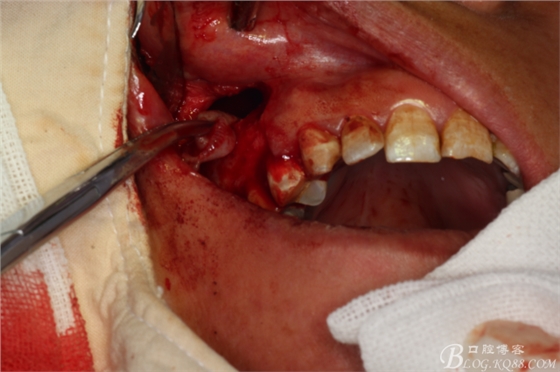

圖8.翻瓣

圖9.暴露出16根尖上方的囊壁

圖10.完整摘除囊壁